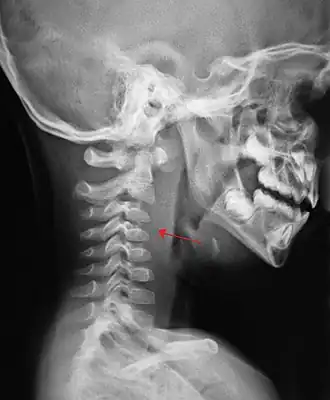

Заглоточный воспалительный инфильтрат (рентгенограмма в боковой проекции)